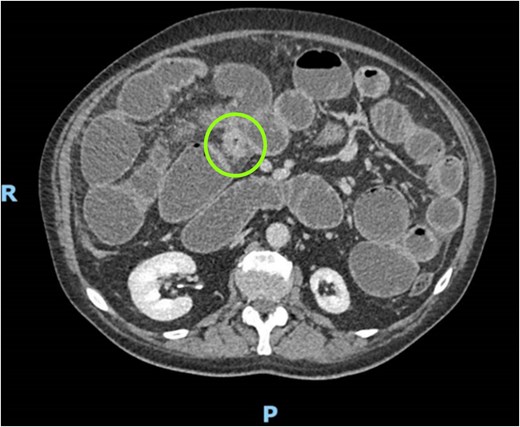

We submitted the patient to a CT scan demonstrating a 10-cm segment of concentric stenosis involving the distal ileum, associated with wall thickening and mesenteric hyperemia, suggesting an inflammatory or ischemic process. The proximal whole small bowel was markedly dilated (Fig. 1).

CT scan demonstrating concentric stenosis (circle) and dilated small bowel.